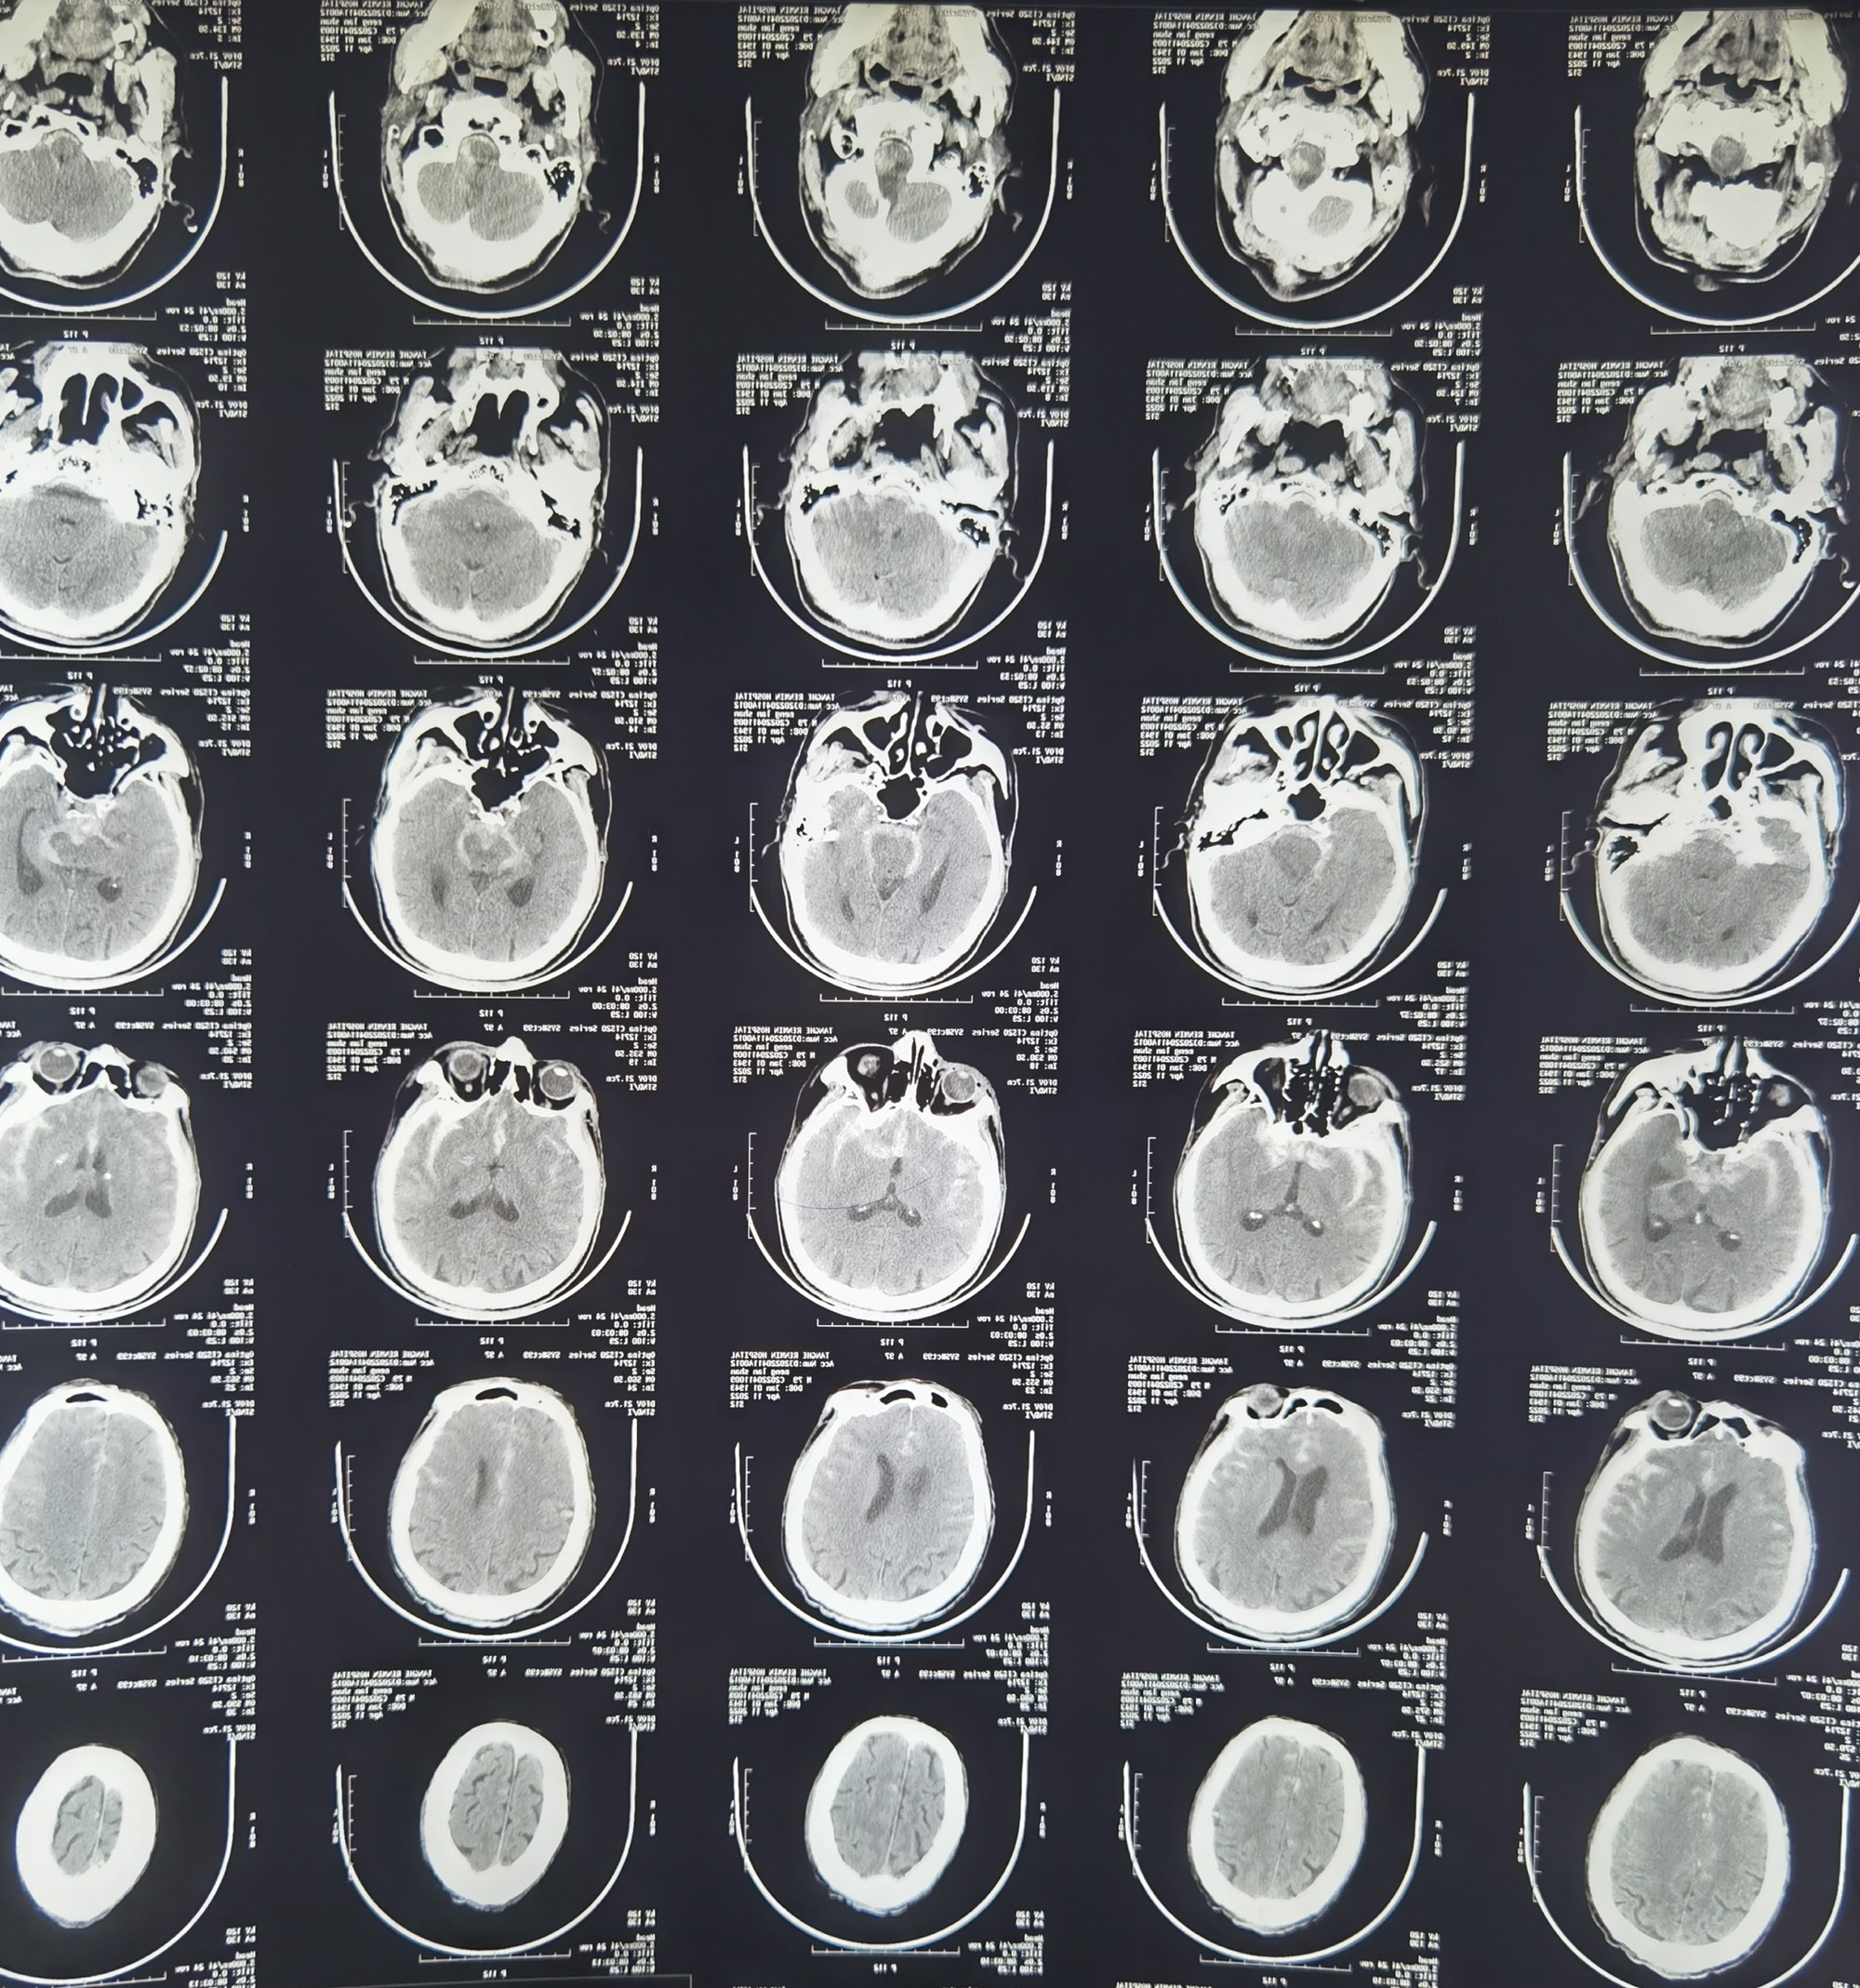

MLS,M79Y,sah,双侧MCA烟雾病,Heubner返动脉瘤,前交通段开窗,细支发出Heubner返动脉,瘤颈细长,瘤颈口比微导管细,弹簧圈2mmx3cm“隔山打牛”填塞治愈,Heubner返动脉保留。

该患者术后2天观察神志清楚,四肢活动正常。